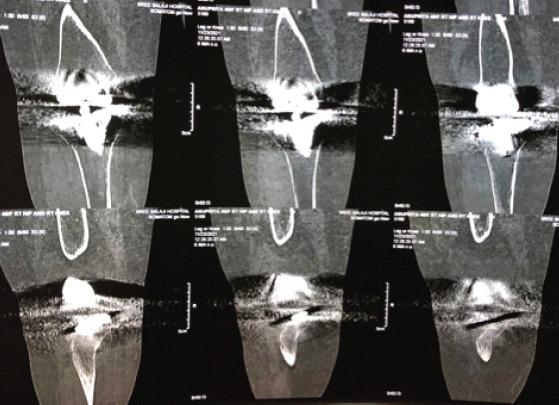

A 52-year-old female with RA sustained a right knee PPF following a trivial fall. Clinical and radiographic evaluation classified the fracture based on prosthetic stability and bone quality:• Type II fracture with a loose prosthesis requiring revision surgery.She underwent staged revision TKA including:1.Definitive surgery with revision TKA and bone grafting in figure.2.Postoperative rehabilitation to restore function figure.

1. 确定性手术,进行翻修TKA并如图所示植骨。

2. 术后康复以恢复功能,如图所示。